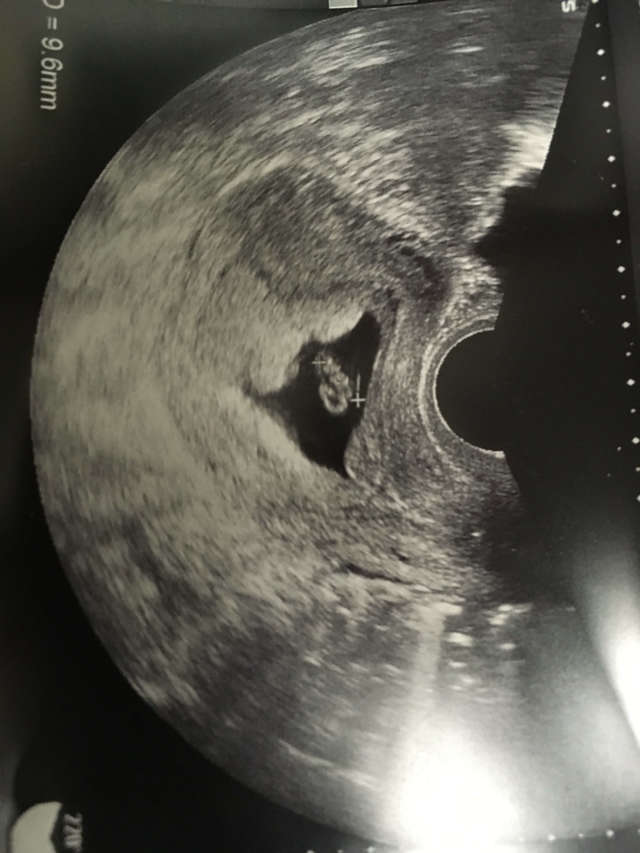

7週0日(7w0d・性別不明)|ありんこ77 さん(35歳)

エコー写真撮影時のエピソード:感動の初対面!なんか酔った感じで熱っポイなとは思っていたが、なかなか妊娠しなかったので、さすがに妊娠してるかもという週までは確認しませんでした。市販の検査薬で反応が出てから1週間後に受診。小さな丸ですが、本当にいるんだと思い、感動の初対面でした。